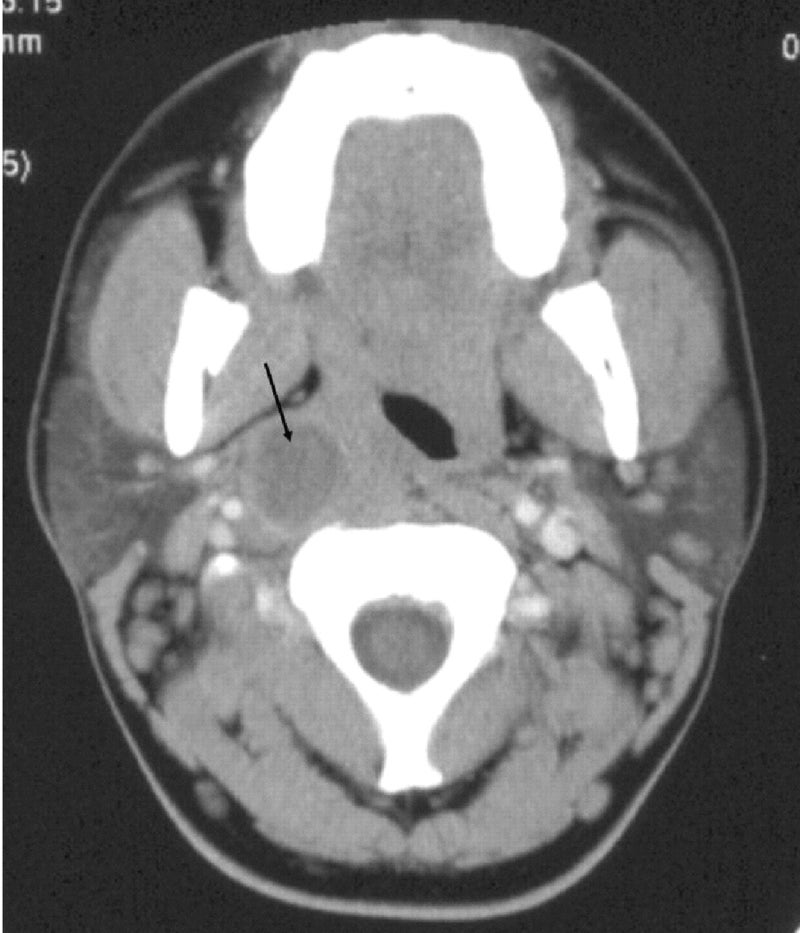

그 중에서도 편도 주위염, 편도 주위 농양 등이 조금 무서운 합병증인데요. 부은 편도 주변에 염증이 파급되어 심각해지는 단계군요. 처음에는 주변 조직이 붓고 아픈 편도 주위염에서 시작하여 염증이 지속됨에 따라 고름이 쌓이는 편도 주위 농양으로 변합니다.

이런 경우 항생제도 바꿔야 하고 심하면 농양 절개를 해야 합니다. 더 방치하면 위아래로 파급되어 깊은 목농양 등으로 확산될 수 있기 때문입니다. 보다 자세한 편도 주위의 농양은 이전 포스팅을 참조하십시오.